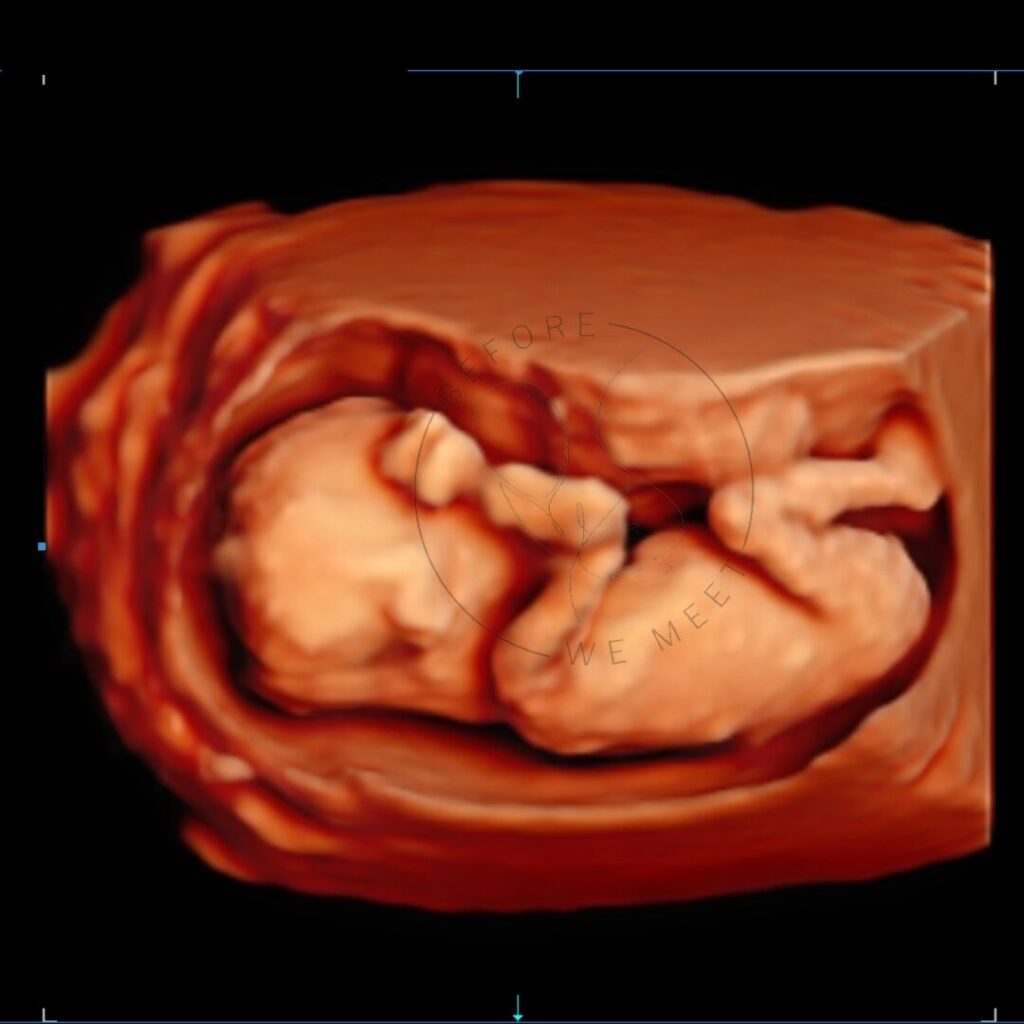

Een 3D/4D echo is éxtra bijzonder doordat we de baby met al zijn of haar details kunnen zien in stilstaande en bewegende beelden. Op wie lijkt zijn/haar neusje? Heeft hij/zij al bolle wangetjes? Of misschien zien we de baby zelfs wel drinken of lachen? Het laat jou (en ons!) verwonderen hoe magisch het nieuwe leven dat in je buik groeit is!

Iedere periode van de zwangerschap vinden wij even bijzonder, juist omdat je per maand zoveel verschil kunt zien. Echter is herkenning van het gezichtje het mooiste tussen de 24e en 30e week van de zwangerschap en afhankelijk van hoe de baby in je buik ligt, of hij/zij zich verstopt achter handjes, voetjes of de placenta en hoeveel vruchtwater er aanwezig is. Mocht het daardoor niet lukken om de baby goed in beeld te krijgen dan mag je nogmaals kosteloos terugkomen voor een echo van 20 minuten.